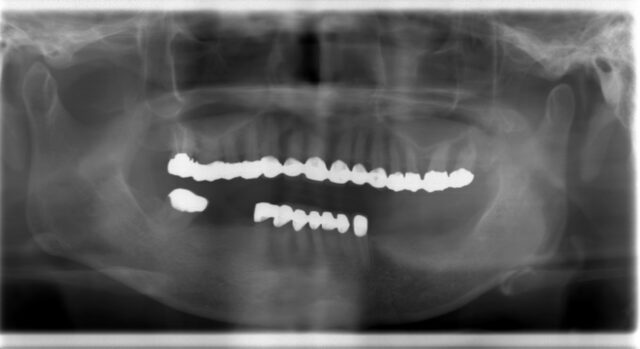

| 通院時の年齢 | 60代 |

|---|---|

| 性別 | 女性 |

| 通院回数 | 3ヶ月 |

| 通院目的 | 入れ歯が嫌なのでインプラントにしたい |

| 処置内容 | 右下65 左下46にインプラント |

| 費用 | 約170万円 |

| 備考 | 昔治療済の歯をそのままに入れ歯の部位のみ治療希望され、十分満足された。 |